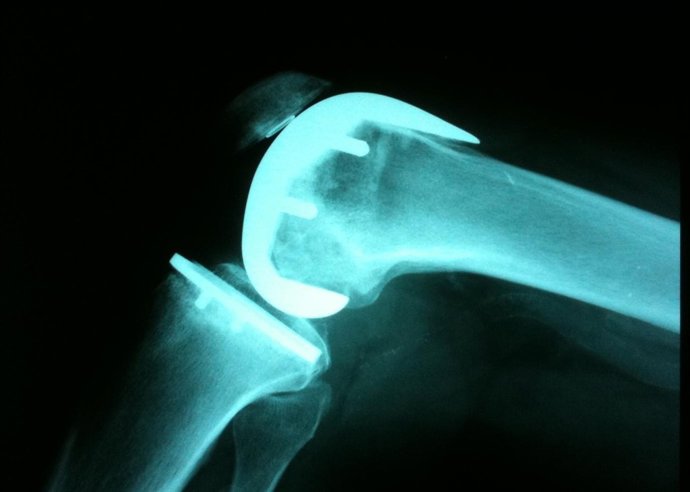

Protesis rodilla

Las prótesis --de rodilla, cadera y columna-- se han implantado en una treintena de hospitales catalanes, entre ellos los barceloneses Sagrat Cor, Quirón y Delfos, aunque el centro más afectado es el Sant Joan de Reus, que tiene constancia de unos 1.500 pacientes con implantes de Traiber, todos en seguimiento médico, informa TV3.